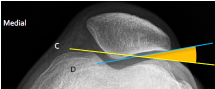

Q what is the name of these lines?

A:

Humeral shaft line : A line drawn through and parallel to the humeral shaft. The yellow line

Ulnar shaft line: A line drawn through and parallel to the ulnar shaft. Blue line

Humeral articular line: A transverse line drawn through the most distal surfaces of the trochlea and capitulum. Humeral Articular line

Q what is the name of this measurement? and what is the average + range?

A: Carrying angle (CA)

assesses the angle between the humeral and ulnar shaft lines. The average is 169°, with a range of 154-178°.

A: Humeral angle (HA) [Elbow]

assesses the angle formed by the humeral shaft and articular lines. The average is 85°, with a range of 72-95°.

A: Ulnar angle (UA)

assesses the angle formed by the ulnar shaft and humeral articular lines. The average is 84°, with a range of 72-99°.